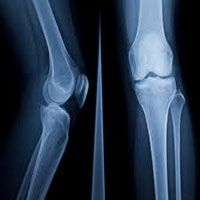

X-rays are routinely used for diagnosis of various bone fractures and bone diseases.

They play an important role in diagnosis of types of fractures and their further management.